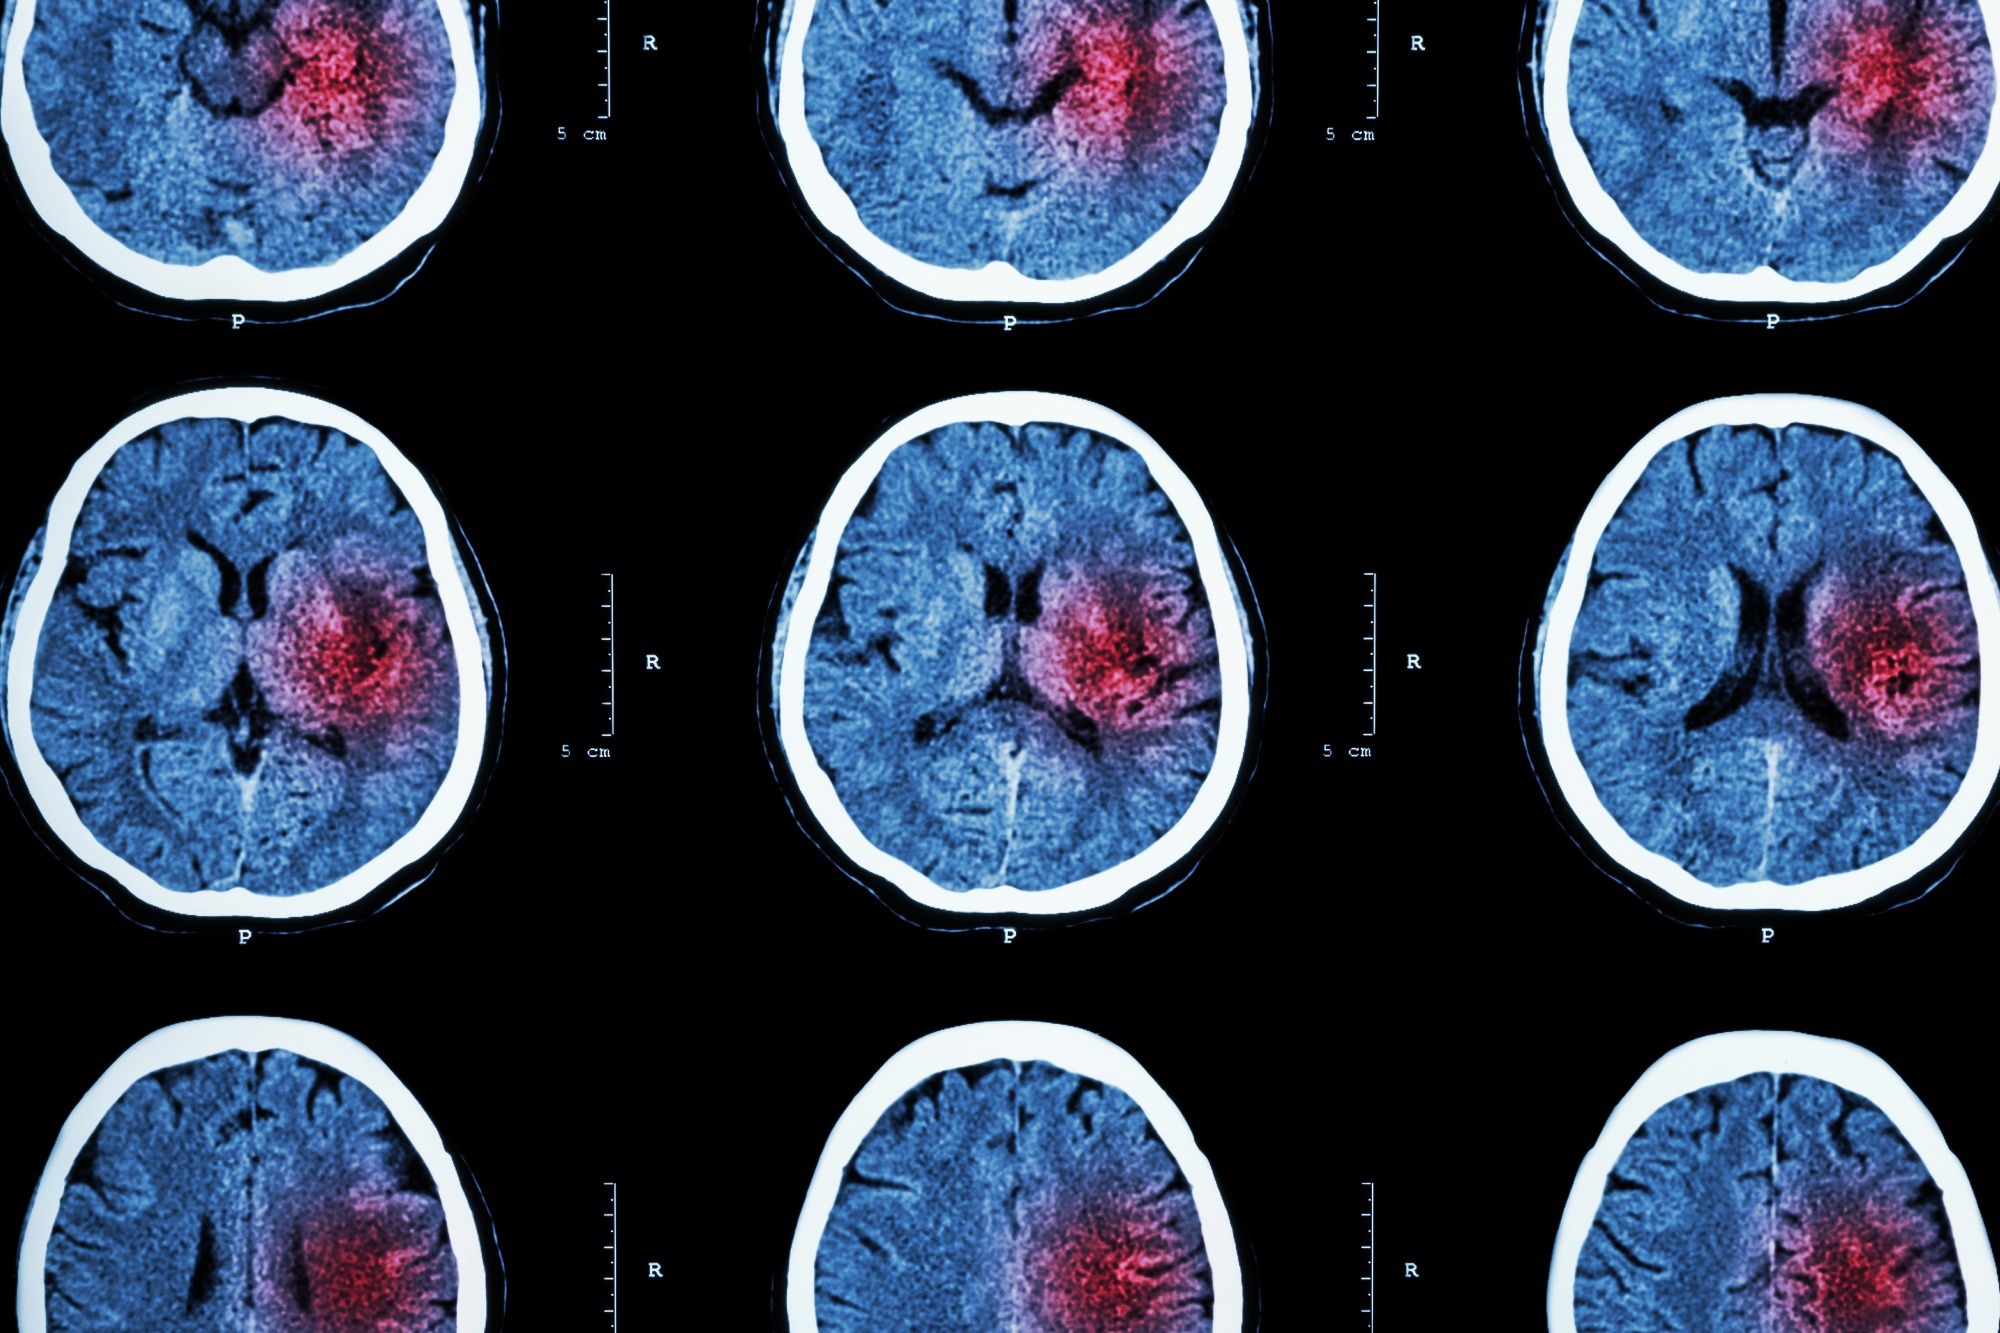

A stroke occurs when a blood vessel that carries oxygen and nutrients to the brain is either blocked by a clot or bursts. Therefore, there are two types of stroke: ischemic and hemorrhagic.

Ischemic strokes – which are the most common and account for 87% of all cases – occur when a blood clot travels to a vessel in the brain and cuts off the blood supply. This prevents brain tissue from getting oxygen and nutrients, and brain cells can begin to die in minutes.

The other type of stroke, hemorrhagic, are often less common than ischemic strokes but can be more severe. These types of strokes are caused by a brain aneurysm burst or rupture of weakened blood vessels.